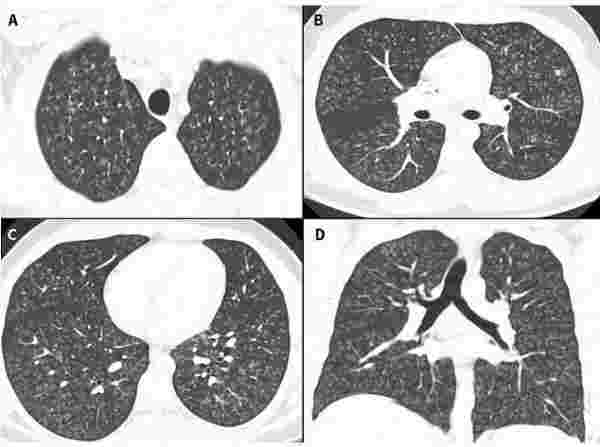

同年,多家海內外媒體報道過一名17歲加拿大少年的病例。該少年出現劇烈咳嗽,被診斷為閉塞性細支氣管炎,繼而惡化為雙肺衰竭,必須進行雙肺移植。影像學檢查顯示,其肺部“就像爆米花一樣,面目全非”。

病史分析發現,罪魁禍首就是電子煙。該款電子煙使用調味劑雙乙酰,一種常見的食用香精添加劑,可以模擬出黃油味。但霧化后,雙乙酰會增加閉塞性細支氣管炎和其他嚴重呼吸道疾病風險。

圖2 17歲少年住院第一天的肺部影像學結果。/Canadian Medical Association Journal